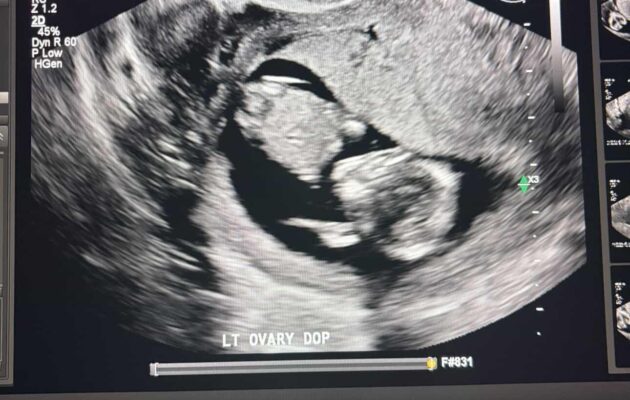

Week 30

Week 30 out of 40 of Pregnancy!